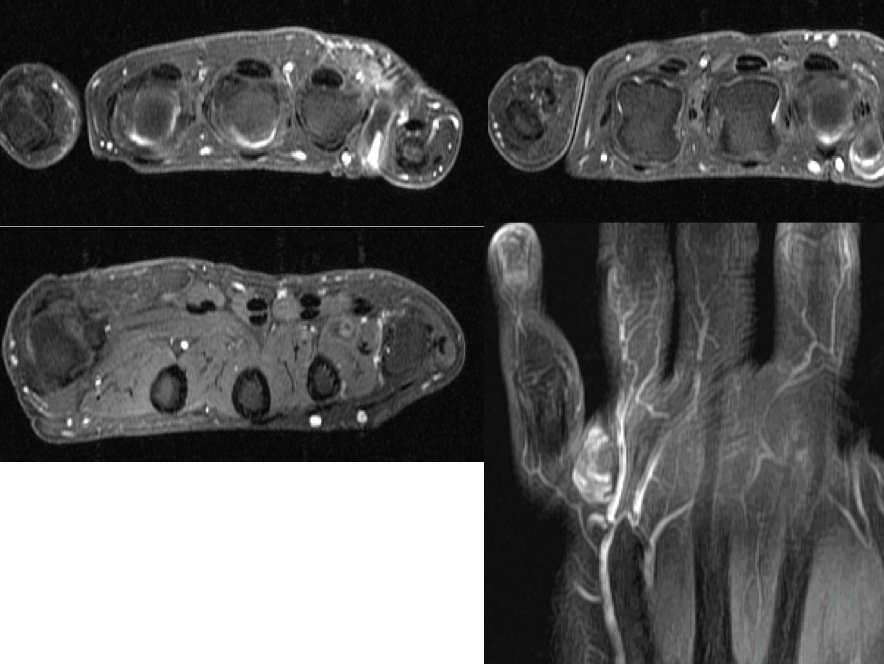

Figure 3 for case Venous malformation ( RID3337 )

Figure 3